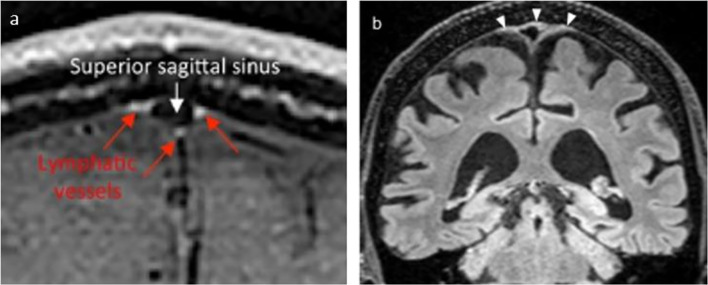

Fig. 4.

Examples of interpretation of lymphatic tissue in parasagittal dura. In a intravenous contrast enhancement in parasagittal dura is interpreted as lymphatic vessels (red arrows), while blood flow in superior sagittal sinus is suppressed (From Absinta et al. eLife 2017) [37]. In b all hyperintense FLAIR-signal in parasagittal dura (arrowheads) was accepted as lymph (From Albayram et al. Nature Communications, 2022) [54]. Figure elements are reused with permission under the Creative Commons International License

A method for a non-contrast approach to visualize meningeal lymph has also been suggested, where literally any hyperintense FLAIR signal outside the brain at MRI was interpreted as lymph [54]. The basis for this understanding was that increasing protein content in an external container was positively associated with FLAIR signal. Since lymph is protein rich, a hyperintense FLAIR signal was therefore accepted to derive from lymph only. As outlined above, the parasagittal dura contains many elements that can contribute to the hyperintense FLAIR signal, including small blood vessels, the lateral lacuna, intradural arachnoid granulations, and the fibrous stroma of the parasagittal dura. Interpretation of a hyperintense FLAIR signal as lymph is therefore highly presumptuous. Furthermore, even hyperintense FLAIR signals from the CSF spaces near the skull base were interpreted as ventral meningeal vessels; however, this has later been dismissed as CSF flow artifacts [55]. Finally, the authors interpreted a continuous, high FLAIR signal in the walls of neck blood vessels as lymph, too, and the continuity with similar signals at the skull base was considered to represent connections between cervical lymph nodes and the intracranial meningeal lymphatic system. A similar interpretation was reproduced in another study from the same group [56]. Again, lymph is not an exclusive source of a high FLAIR signal, and for instance connective tissue and vasa vasorum in neck vessel walls are least as likely sources. Ultimately, the reasoning behind accepting any structure with high FLAIR signal outside brain as lymph was heavily contested by two independent commentaries [55, 57]. Examples of contrast and non-contrast based interpretations of lymph at MRI are given in Fig. 4.

To exclude venous signals at MRI, “black blood” techniques have been applied to darken signal from slow flow within the venous vasculature [41]. However, shine-through of signal from veins with very slow flow, or artifacts from slow flowing blood in smaller vessels is one major confounding factor in the interpretation of high signal in tubular structures [51]. Whereas accompanying contrast-enhanced MR venography has further been added to subtract signals from veins that were visible at MRI [41], venous structures of microscopic size with very low flow velocity, or having caliber well below the image resolution, may not be depicted. Still, diffuse contrast enhancement in parasagittal dural regions was widely interpreted as lymph. However, blood vessels in the dura lack tight junctions and allow extravasation of solutes as large as 43 kDa [52], while for instance gadobutrol has molecular weight ~ 0.6 kDa [40]. Therefore, intravenous contrast is expected to enhance in the extra-vascular stroma of the parasagittal dura through these abundant, leaky vessels. Further sources of contrast enhancement in the parasagittal dura, whether diffuse or in shape of tubular vessels, may be derived from enrichment within networks of dural veins and capillaries, and also as proposed by Park et al. [32], enrichment within intradural channels. Absinta et al. [37] observed that a blood pool agent (gadofosveset) did not leak into the parasagittal dura, contrary to the enhancement which was observed in dura after intravenous administration of gadobutrol. Even though the enhancement they observed may be considered diffuse and at millimeter scale as revealed by 2D (Fig. 4) and not least by 3D representations, and qualitatively comparable to the enhancement in the choroid plexuses, they interpreted this as lymphatic vessels.